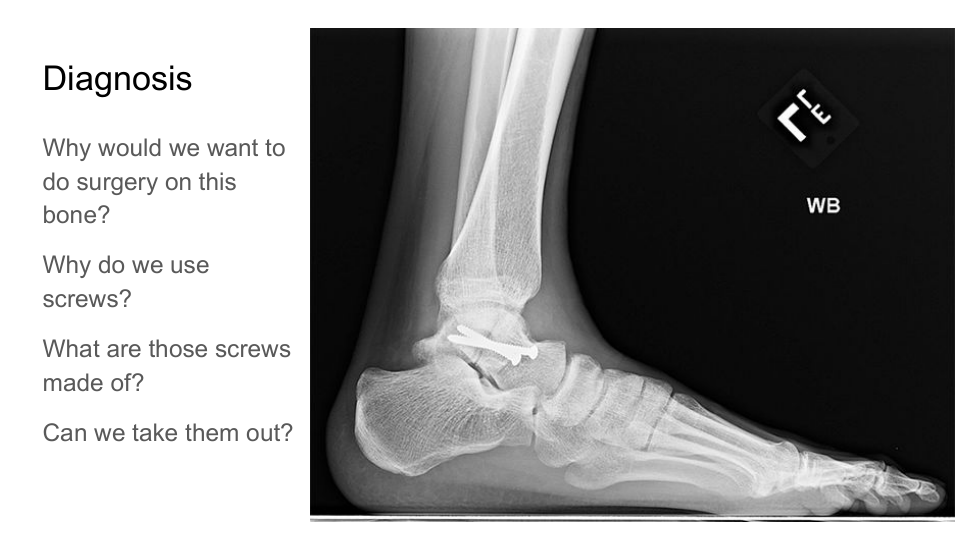

what structure is broken?